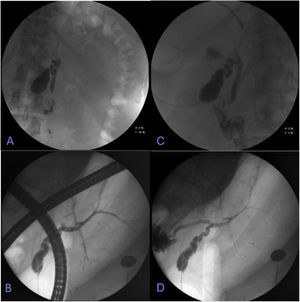

Endoscopic retrograde cholangiopancreatography (ERCP).

Cholangiography carried out through the “T” tube, with water-soluble contrast medium. A and B) Entrance of contrast medium with opacification of the gallbladder, in a central anatomic position, slightly to the left of the midline. C and D) Cystic gallbladder containing stones and intrahepatic bile duct located on the left, with no alterations, no signs of biliary filling defects, and with adequate passage of the contrast medium into the duodenum.